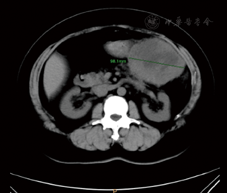

术后仁济医院放疗23次,放疗剂量46 Gy分23次。定期我院随访,2018年4月18日复查CA125为48.54 U/ml,略高于正常;8月15日复查CA125为24.65 U/ml。2019年6月自觉左上腹隐痛,于6月27日行腹部增强MRI,提示胃、胰尾及脾间隙内见一大小约103.5 mm×78.0 mm软组织占位,间皮瘤可能,横结肠系膜、大网膜多发小节结影,种植改变?腹膜后淋巴结增大(图1,图2,图3)。